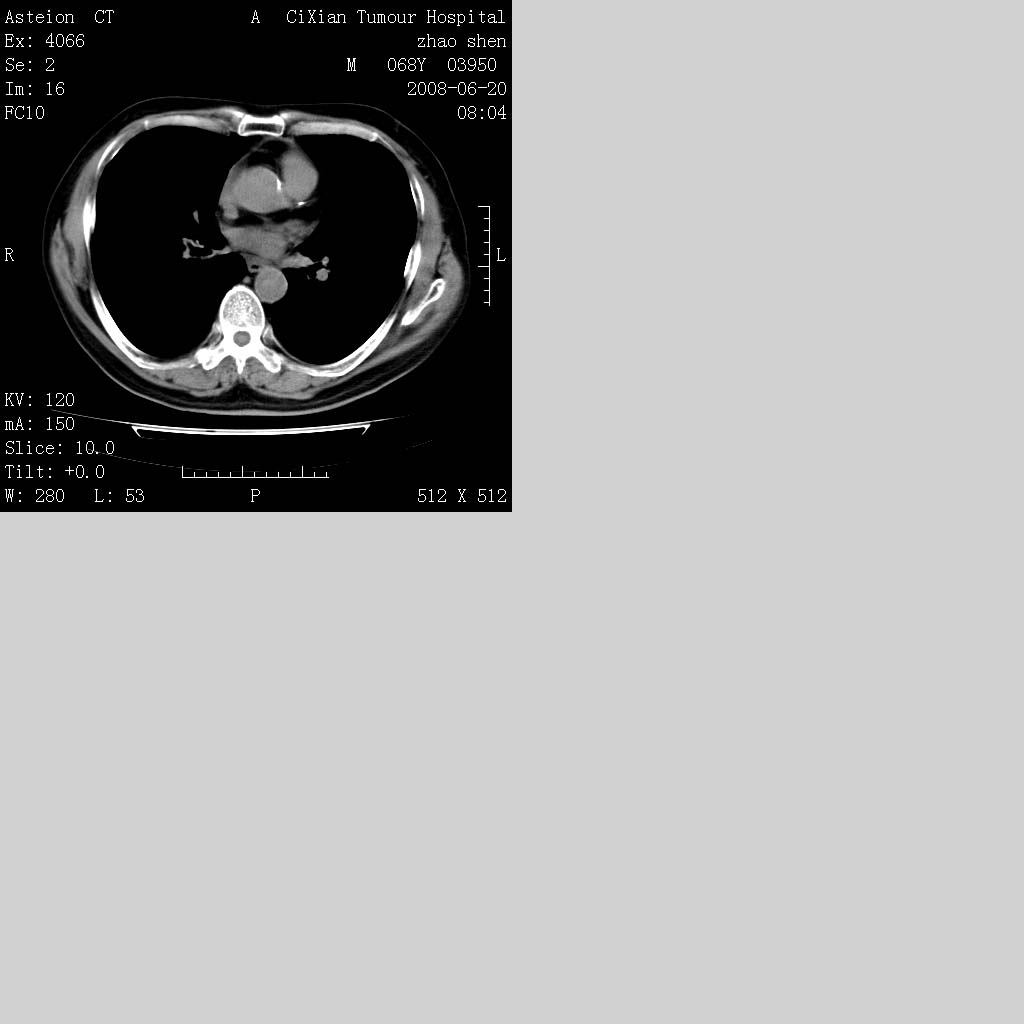

以下是引用守望可可西里在2008-6-24 1:11:00的发言:[br][br] 考虑为周围型肺癌:[br] 1.分叶结节,形态极不规则,蟹足样伸展的恶性浸润特征比较明确。[br] 2.磨玻璃影中由多个更高密度小结节聚集呈梅花瓣样。[br] 3.局部胸膜凹陷征比较明确。[br][br] 另:纵隔胸膜明显增厚、粘连。

以下是引用zjzjr在2008-6-24 11:19:00的发言:[br]支持左下肺周围型肺癌伴右肺转移,纵隔淋巴结转移,心包积液.

以下是引用zhangling在2008-6-24 14:56:00的发言:[br]我们科室意见报告为[br][br]1考虑左下肺周围型肺癌[br]2右肺小结节考虑转移瘤,纵隔淋巴结转移[br]3心包积液. [br] 各位老师分析的相当好 谢意[br]